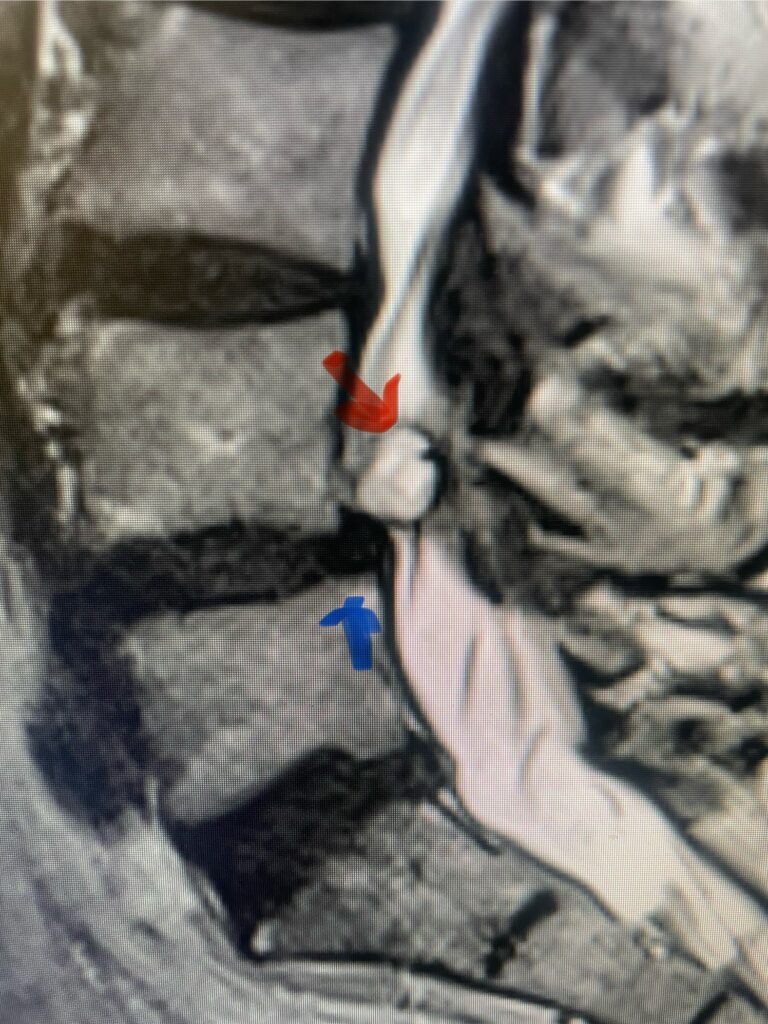

Here is a tough case: This is a 72 year-old male who presented with several months of progressive neck pain without symptoms of the arms or legs. […]